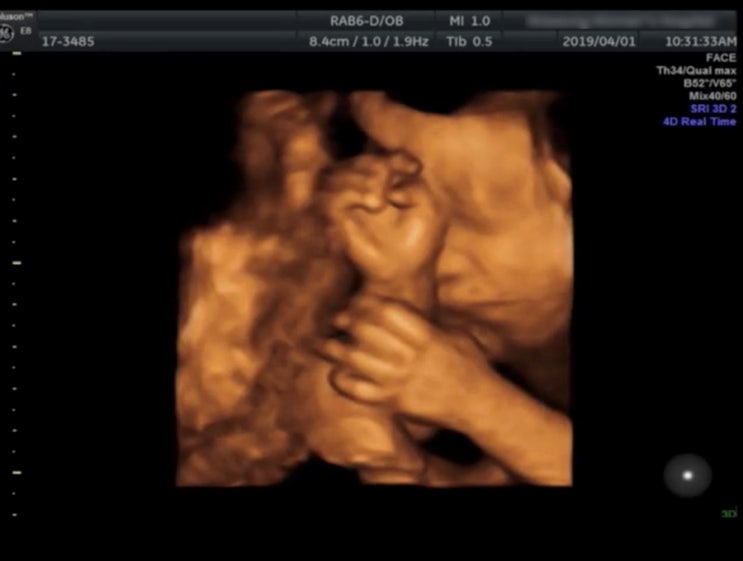

2016년 12월 10일에 결혼식을 올린 우리 부부 :) 첫 번째 결혼기념일엔 홍콩으로 여행을 떠났었다. 2017. 1...